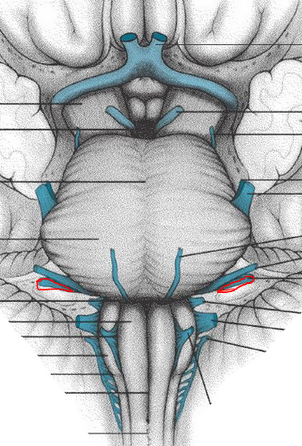

optic tract

visual radiation

prectum

superior colliculis

occulomotor

occulomotor nerve

lateral geniculate n.

damage to optic nerve – effect on pullairy light reflex

+ light in pislateral eye

Damaged optic nerve – light in ipsilateral eye =

NO direct, NO consensual

+ light in contralateral eye

Both direct and consensual INTACT

damage to occulomotor nerve/EW nucelus

+ light in ipsilateral eye effects

= NO direct, but the consensual is INTACT

Damaged oculomotor nerve /EW nucleus

+ light in contralateral eye =

Direct INTACT, NO consensual

Damage to medial midbrain (ie. Bilateral Pretectal nuclei and/or both EW nuclei)